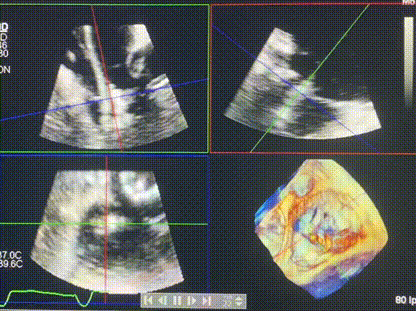

術(shù)后DSA顯示Lux-Valve Plus與Tendyne和ICD無(wú)相互影響

術(shù)后超聲顯示僅殘余微量瓣周漏

LuX-Valve Plus經(jīng)血管三尖瓣置換系統(tǒng)此次“出海”圓滿完成,術(shù)后Rodrigo Estévez-Loureiro教授對(duì)LuX-Valve Plus經(jīng)血管三尖瓣置換系統(tǒng)的器械性能和治療效果大為稱贊,認(rèn)為L(zhǎng)uX-Valve Plus的手術(shù)體驗(yàn)非常好。術(shù)后即刻超聲顯示三尖瓣反流幾乎完全消失,血流動(dòng)力學(xué)改善顯著,患者恢復(fù)快。在面對(duì)復(fù)雜解剖結(jié)構(gòu)、超聲影像質(zhì)量不佳、有起搏導(dǎo)線干擾時(shí),Lux-Valve Plus也體現(xiàn)了極強(qiáng)的適應(yīng)性。Thomas Modine教授和Anson Cheung教授也肯定了LuX-Valve Plus術(shù)中操作的便捷性,認(rèn)為L(zhǎng)uX-Valve Plus容錯(cuò)率高,對(duì)術(shù)中影像的依賴較小,后期希望可以更多的應(yīng)用LuX-Valve Plus三尖瓣置換系統(tǒng)于臨床實(shí)踐,讓更多的三尖瓣重度反流患者盡早獲益,改善預(yù)后。